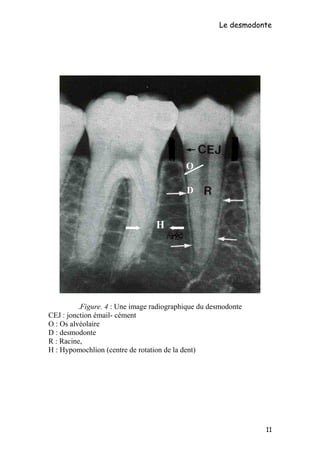

Le desmodonte se situe entre l'os alvéolaire et le cément ; sa largeur dans

les conditions physiologiques est de 0,15 à 0,38 mm (elle varie suivant

l’âge et la fonction). Il présente un rétrécissement au un tiers apical qui

lui donne une forme en sablier. C'est à ce niveau que se situe

l’hypomochlion (centre de rotation de la dent) (cf. Figure 4).

Figure. 4 : Une image radiographique du desmodonte.

CEJ : jonction émail- cément

O : Os alvéolaire

D : desmodonte

R : Racine,

H : Hypomochlion (centre de rotation de la dent)